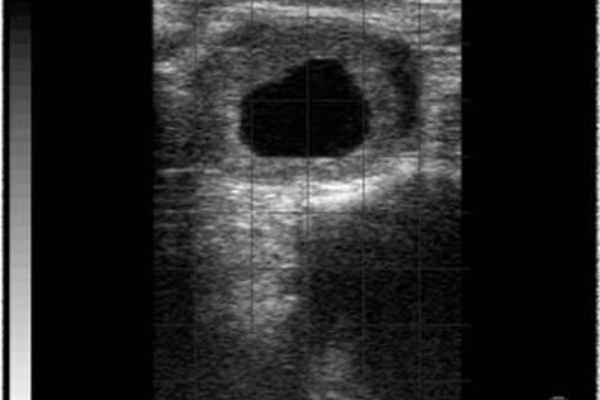

- Yumurtalıklarda oluşan kistler: Yumurtalıklarda çeşitli sebepler dolayısıyla kistleşen yapılar meydana gelirse bu yapılar uygun şekilde tedavi edilmeden hayvanın gebe kalma ihtimali normalden daha düşük olacaktır.